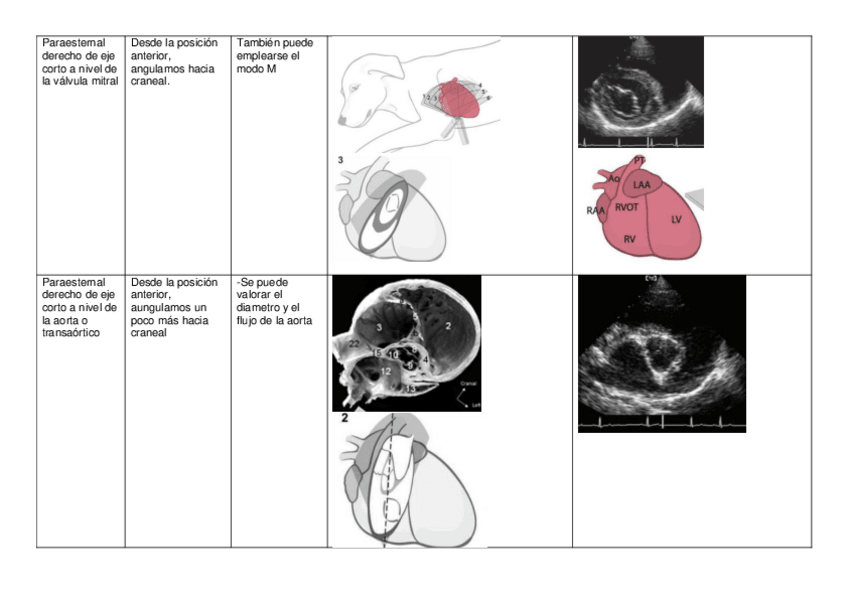

He publicado nuevos apuntes de 3º Diagnóstico Por la Imagen: Tablas-ecocardiografia.pdf